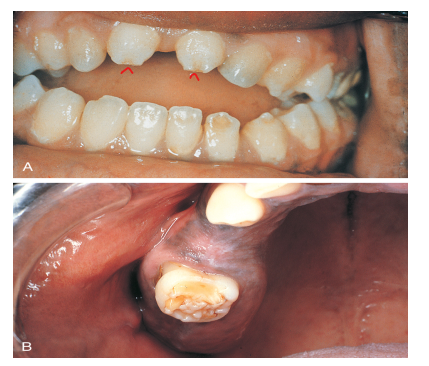

<p>Various degrees of disability due to improper development of the palate. </p>

Various degrees of disability due to improper development of the palate.

What is cleft palate? How is it formed?

Cleft palate is the failure of lateral palatine processes fusion with each other or with the premaxilla (primary palate)

• causes nasal cavity to be exposed to oral environment

• more common in females

• hereditary influence may be a factor

• other etiological factors may include: mechanical interference by the tongue, stress, infectious disease, malnutrition, increasing maternal age.